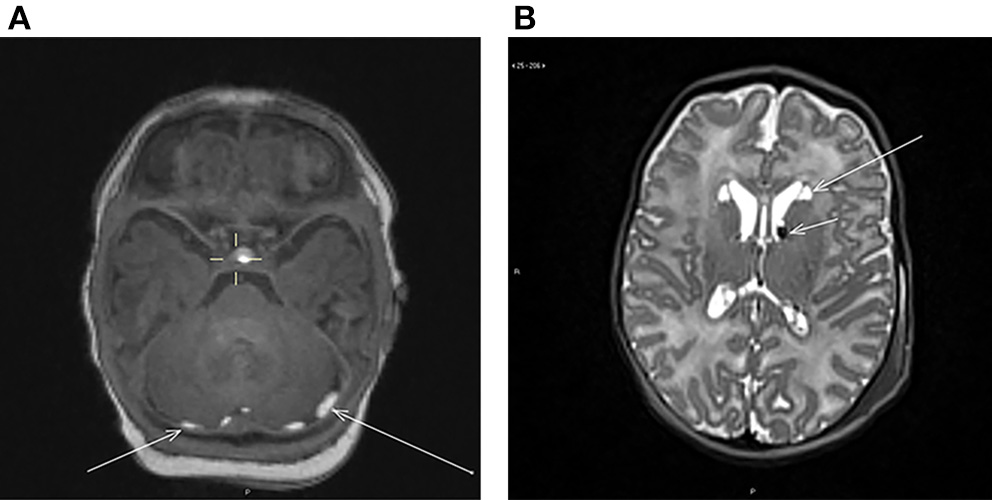

The findings included subdural and intraparenchymal hemorrhages, cysts and their co-existence. Out of all the incidental findings, subdural hemorrhages had the highest prevalence (n = 10, 5.7%). Subdural hemorrhages were mostly located in multiple sites (Table 2). The majority (n = 10) was located in the posterior fossa (Figure 1), but also temporal (n = 4) and occipital (n = 3) hemorrhages were detected. The temporal subdural hemorrhages coincided mainly with hemorrhages located in the posterior fossa and in the occipital lobe (3 out of 4). Two infants with subdural hemorrhages had also additional parenchymal involvement; one cyst-associated hemorrhage in the caudo-thalamic region (Figure 1) and one hemorrhage in the cerebellar region, respectively. Furthermore, one independent cerebellar parenchymal hemorrhage, one caudo-thalamic cyst and one caudo-thalamic cyst combined with a parenchymal hemorrhage were observed. The one infant with an independent caudo-thalamic cyst was excluded from the subsequent analyses due to the high prevalence of these cysts in normal brain development (7, 8), and as birth-related factors are likely uninvolved in their occurrence. The distribution of the hemorrhages is described in Table 2 and examples of a posterior fossa hemorrhage and a cyst associated with hemorrhage are given in Figure 1.

Figure 1. (A) Axial T1-weighted image showing bilateral subdural hemorrhages (arrows) in the posterior fossa behind the cerebellum. (B) Axial T2-weighted image showing bilateral cysts at the head of nucleus caudatus (long arrow) and bilateral hemorrhages at the caudothalamic groove (short arrow).